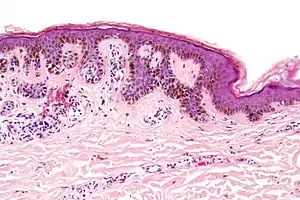

Characteristic rete ridge bridging, shouldering, and lamellar fibrosis. H&E stain. |